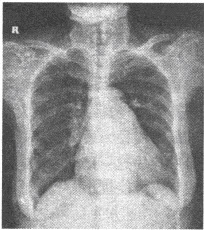

患者,男,30岁,寒战、高热、咳嗽、气促4天。4天前受凉后突然出现寒战、高热,体温40℃,以午后、晚间为重,咳嗽,咳暗红色血痰,右侧胸痛,深吸气及咳嗽时加重,伴气促。右上肺叩诊浊音,语颤增强,可闻及支气管呼吸音。血WBC19×10

9

/L,N90%。

第1题,共3个问题

(单选题)病变在X线下最可能的表现为()

A:呈片状或三角形致密影,致密影内可见支气管充气征

B:呈斑片状模糊致密影,密度不均

C:呈网状及小斑片状影

D:呈浓密的团块状影

E:呈局限性斑片状阴影

第2题,共3个问题

(单选题)针对上述临床症状及体征,最可能的诊断是()

A:大叶性肺炎

B:支气管肺炎

C:支原体肺炎

D:过敏性肺炎

E:金黄色葡萄球菌肺炎

第3题,共3个问题

(单选题)首选的影像学检查是()

A:CT

B:B超

C:胸部平片

D:MRI

E:支气管碘油造影